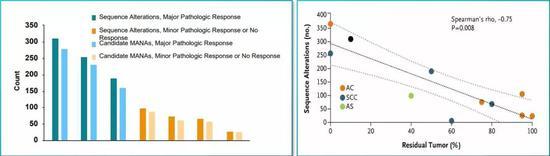

而手术前使用O药,确实调动了患者体内的T细胞进入抗肿瘤免疫状态,病理切片也证实,大量的T细胞和巨噬细胞浸润到了肿瘤当中。患者的肿瘤突变负荷(TMB),则有望作为预估疗效的生物标记物[10]。

基本上呈现的是一种线性关系,突变多疗效就好

当然,机遇和挑战同在。拿生物标记物来说,肿瘤突变负荷(TMB),在CheckMate-159试验中就与患者的新辅助疗效有关,突变数量越多,疗效就相对越好,这也符合了免疫新辅助治疗利用大量新抗原的道理。